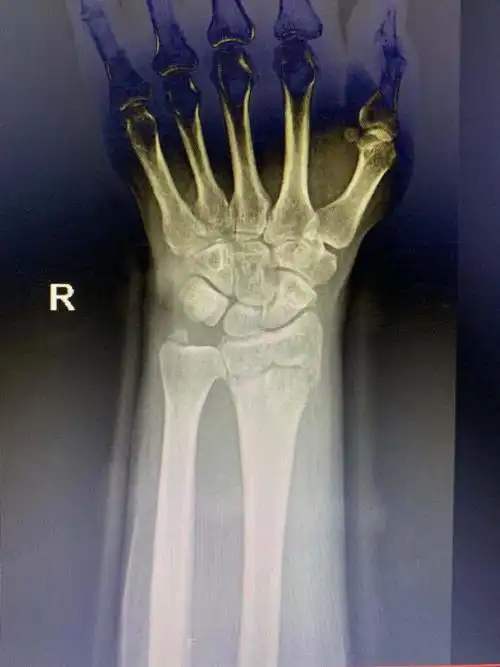

男孩,9岁,右桡骨远端骨折

右侧桡骨远端骨折